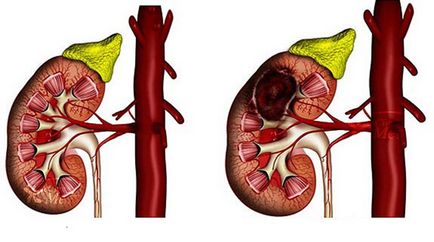

Az eredmény ez a betegség válik vesenagyobbodással, ami oka lehet:- kövek jelenlétét;

Miután érzékelte, renális diffúziós kell végeznie teljes vizsgálatának a test fejlesztés különböző patológiás állapotok és másodlagos betegségek. Ezek a betegségek módosítások kíséretében vese méretének. Jelenlétében semmilyen akut vese betegségek növekvő átmérőjű, ami megnehezíti a közeli szervekben. Során súlyosbodása krónikus betegség megfigyelt elvékonyodása parenchyma, ami tovább jár csökkent a renális héj vastagsága.

Parenchymás vese ciszta

Amellett, hogy változások a vesében járó diffúziós, tumorok és ciszták hatással lehet a feltétele a szervezetben. Ciszta parenchyma jobb vagy bal vese - a kezelendő betegség végezhetjük segítségével gyógyszerek vagy műtét. Ezek a formációk egyetlen vagy többszörös üregek folyadékkal töltött, és amelynek mérete 3-5cm. Fokozatosan bővülő ciszta mérete megnő a vese, ahol alakult.

Ha elég nagy, ez az oktatás kezd jelent közvetlen veszélyt a szomszédos szervekhez, ami befolyásolja a munkájukat préseléssel. A kis ciszták lehet eltávolítani a hagyományos terápiák, amelyek az orvos által előírt után különböző felmérések a laboratóriumban. Ha a ciszta nő a nagy méretű, ez lesz a veszélyt más szervekre, és sebészileg el kell távolítani.